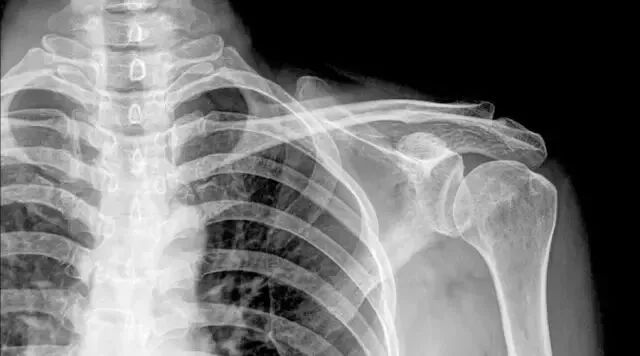

冻结肩,就是我们老百姓俗称的肩周炎

在美国叫做:“Frozen Shoulder”。肩周炎,又称肩关节周围炎,俗称:寒凝肩、五十肩、漏风肩。

上图为肩周炎疼痛弧